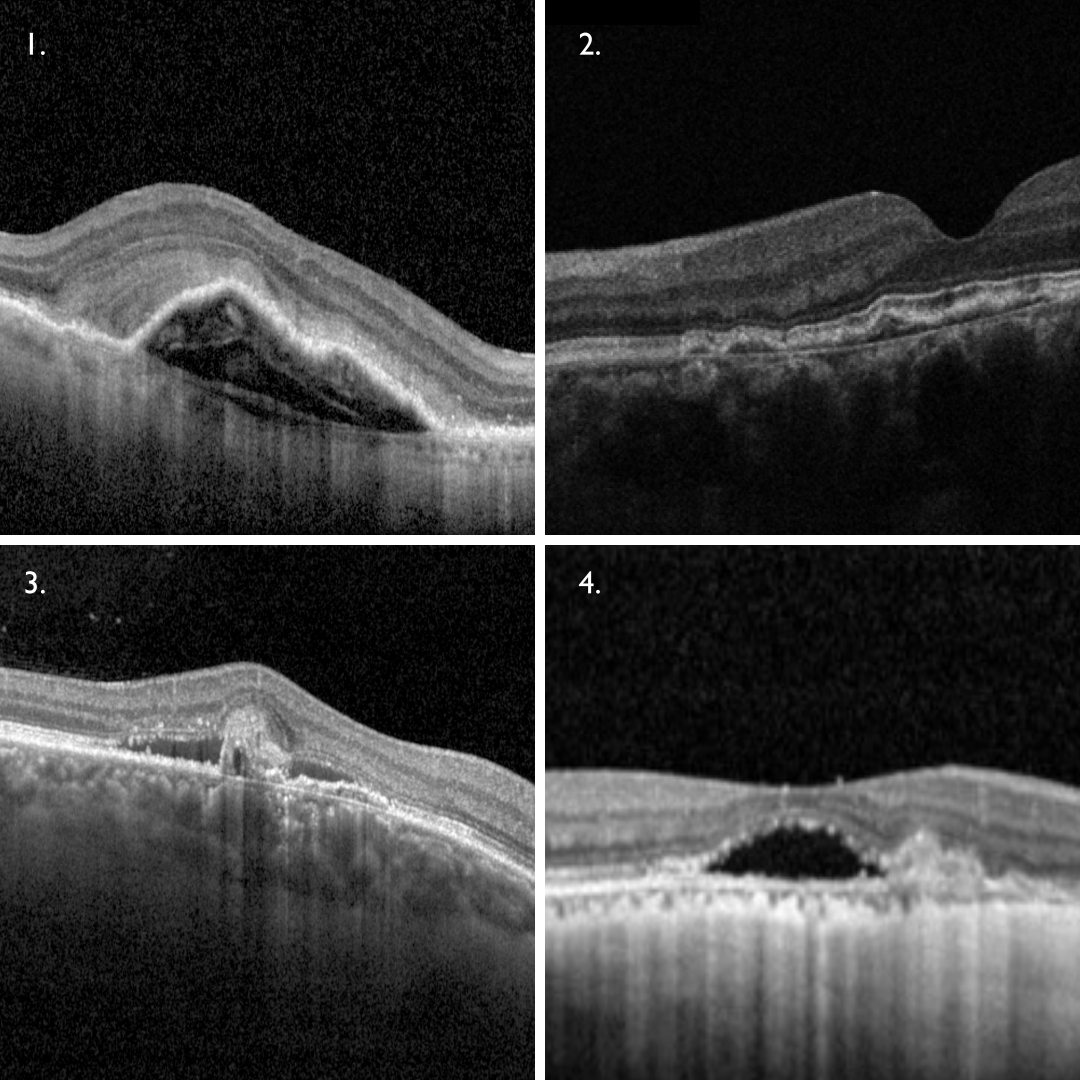

- In AMD, the CNV breaks through Bruch’s membrane, sending branches out laterally underneath the RPE, elevating this layer (1).

- In pachychoroid disease, Type 1 CNV can occur in chronic CSCR, pachychoroid neovasculopathy (2) and polypoidal choroidal vasculopathy (3). In these cases, the choroidal neovascular membrane lies within a flat, irregular pigment epithelial detachment (FIPED) on OCT imaging. In cases of polypoidal choroidal vasculopathy, additional findings such as a sharp peaked PED and subretinal or intraretinal fluid can be seen.

Myopic CNV is a common form of Type 2 CNV with the neovascular network proliferating into the subretinal space. It appears as a highly reflective area above the RPE (4). There is typically minimal subretinal fluid associated with this type of neovascularisation.